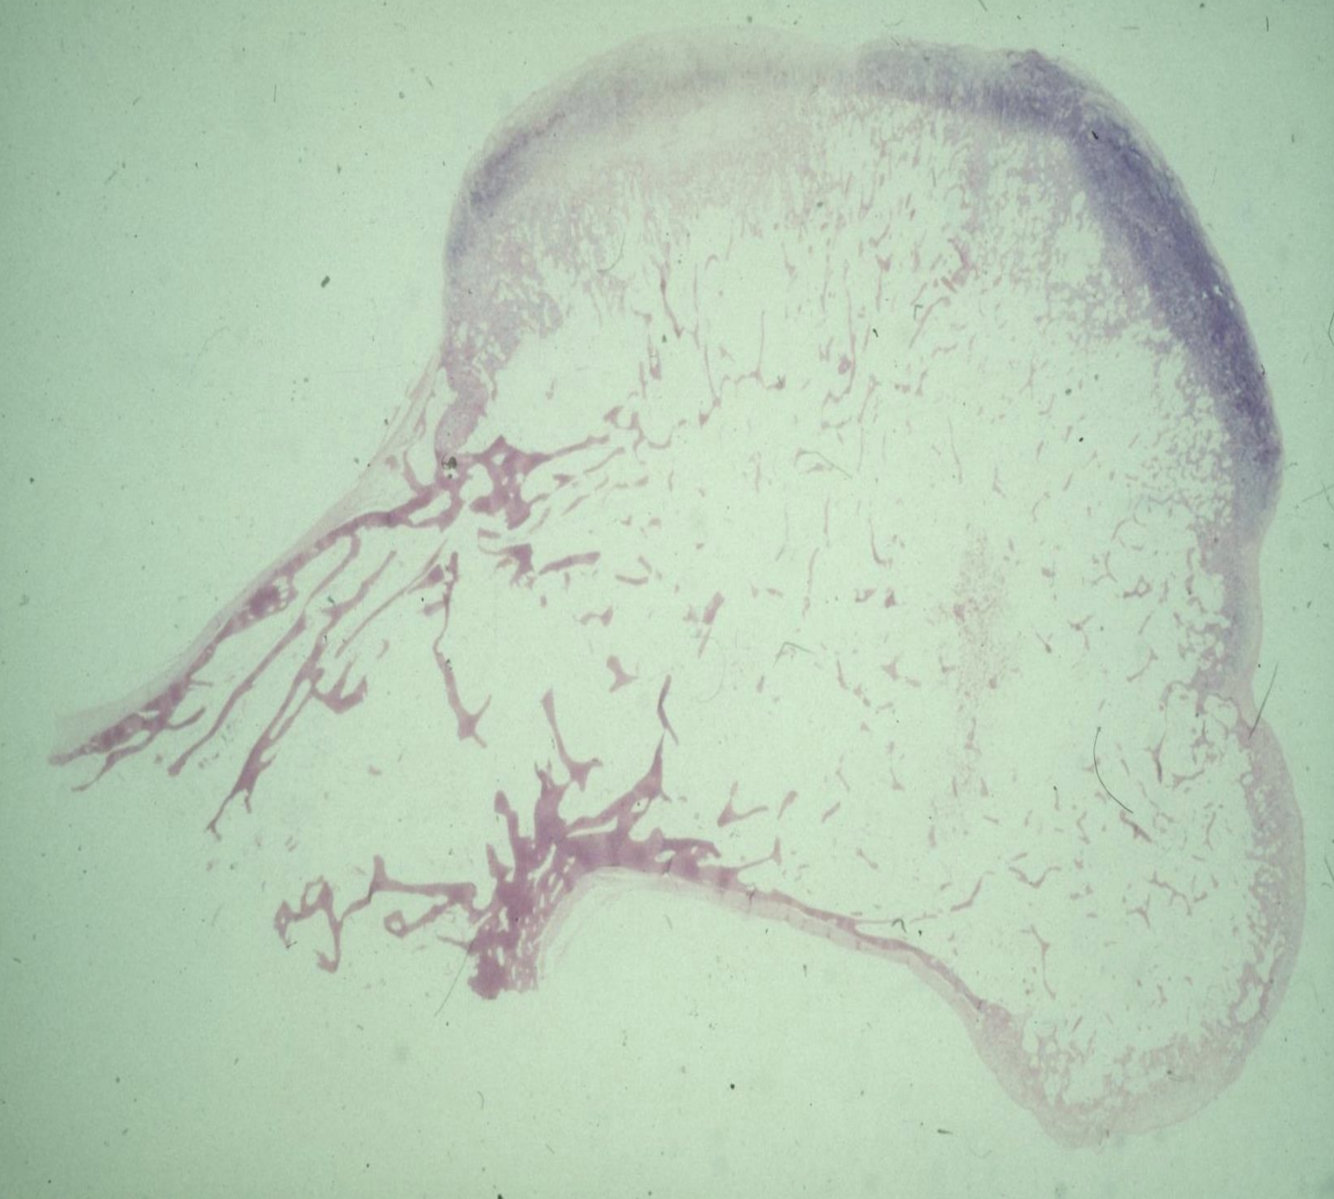

Bone histology of a lesions shows

Cartilage capped “mushroom” bony outgrowth - what is the diangosis?

Osteochondroma

Show’s normal bone covered by cartilage